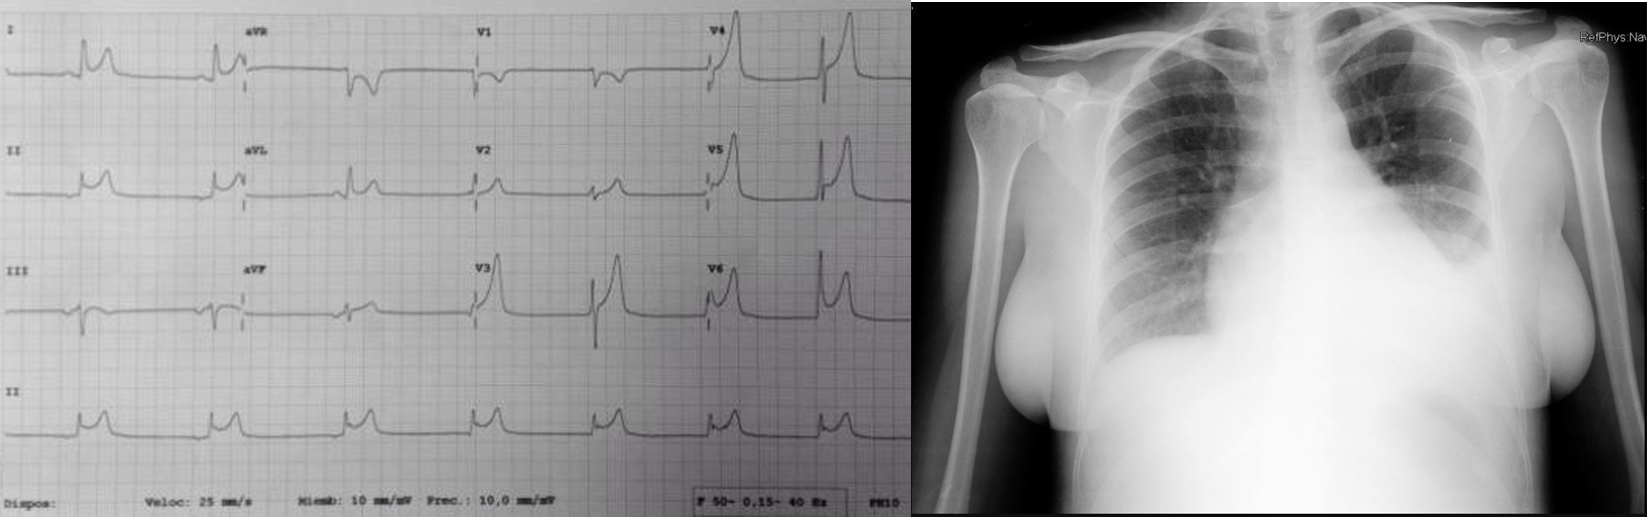

3. Describa el electrocardiograma y la radiografía de tórax realizadas en urgencias.

3. Radiografía de tórax: Silueta cardíaca y parénquima pulmonar de aspecto normal. Ocupación del seno costo-diafragmático izquierdo. Probable derrame pleural izquierdo.

Electrocardiograma: Ritmo auricular bajo (P negativa en cara inferior) a 48 lpm. Descenso del PR difuso. QRS estrecho con eje cardíaco normal. Elevación del ST en guirnalda de V3-V6, I-II-AVL.